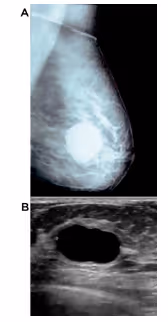

Cistos mamários

Frequente na faixa dos 35 a 40 anos. São lesões dolorosas, redondas, bem delimitadas, móveis, de consistência mole ou endurecidas, de crescimento rápido. Ocorre uma obstrução do ducto e acumula-se líquido. No exame de imagem: lesões circunscritas, anecoicas, com reforço acústico posterior. A conduta é esperar que o tumor regrida espontaneamente.

Se cistos muito pequenos, espessos e muito dolorosos é necessário a punção aspirativa por agulha fina (PAAF) para definir o diagnóstico. O risco de malignidade é menos de 0,1%. Ele é classificado em cistos simples (considerar punção aspirativa se maior de 2cm e seguimento anual), complicado (ou espesso seguimento anual) ou complexo (é sólido é necessário biópsia ou exérese).

Figura 1.1 – Cisto mamário

Fonte: (A) Giant breast cyst: a rare clinical entity, 2018; (B) A Study and Analysis of Hybrid Intelligent Techniques for Breast Cancer Detection Using Breast Thermograms, 2015.